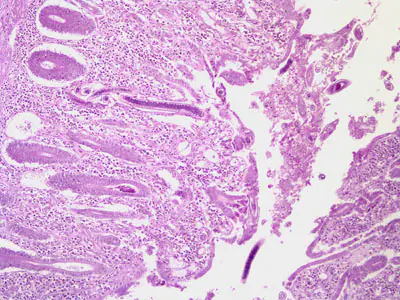

A 49-year-old Filipino man had an intestinal tissue biopsy taken. Figures A-C show what was seen on slides stained with hematoxylin and eosin (H & E). Figure A was taken at 100× magnification, Figure B was taken at 400× magnification, and Figure C (of a different section) was taken at 1000× magnification. Figure D was taken from a wet mount slide of formalin preserved stool; the object of interest in Figure D is approximately 40 micrometers long by 20 micrometers wide. What is your diagnosis? Based on what criteria?

Figure A